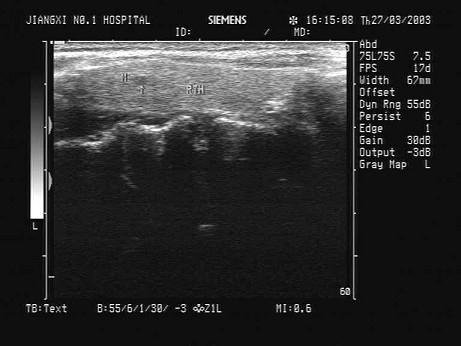

问题 患者发现颈部肿块两年余,无明显不适。甲状腺超声显示甲状腺及血管旁异常光团,如图。最可能的诊断为?(?)

选项 A.甲状腺癌 B.结节性甲状腺肿 C.甲状腺炎 D.甲状腺腺瘤 E.以上均不是

答案 A